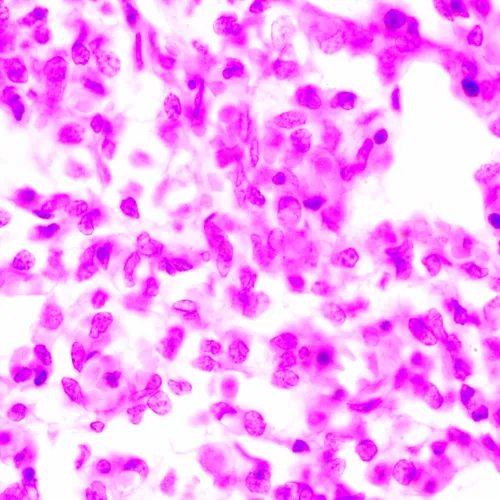

Mikroskop klasy badawczej. Model jest przeznaczony do obserwacji przezroczystych i półprzezroczystych preparatów biologicznych, takich jak rozmazy i przekroje poprzeczne, w świetle przechodzącym w jasnym polu. Zamontowanie dodatkowych akcesoriów umożliwia prowadzenie obserwacji metodami ciemnego pola, kontrastu fazowego, fluorescencji i polaryzacji.